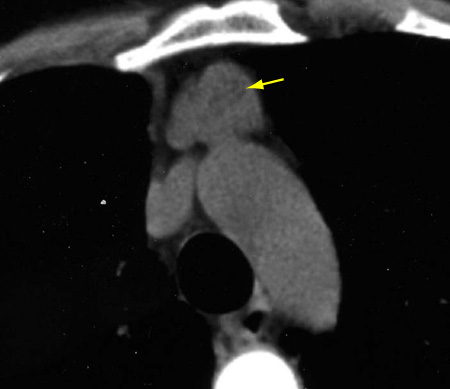

Chest CT usually shows enlargement of the typical shape of the thymus (bilobed) without a dominant or discrete rounded mass. [Figure caption and citation for the preceding image starts]: CT scan of the chest showing a prominent thymic gland with bilobed appearance, consistent with thymic hyperplasiaFrom the collection of Cameron Wright, MD; used with permission [Citation ends].